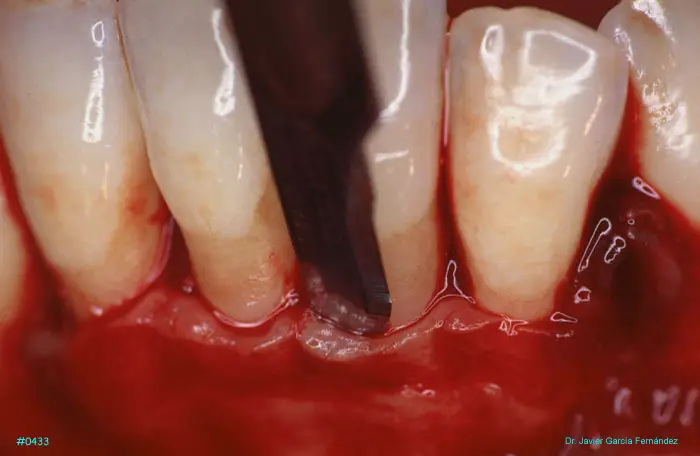

Atlas of Surgical Techniques in Periodontics. Chapter II. Atlas de Técnicas Quirúrgicas en Periodoncia

image54